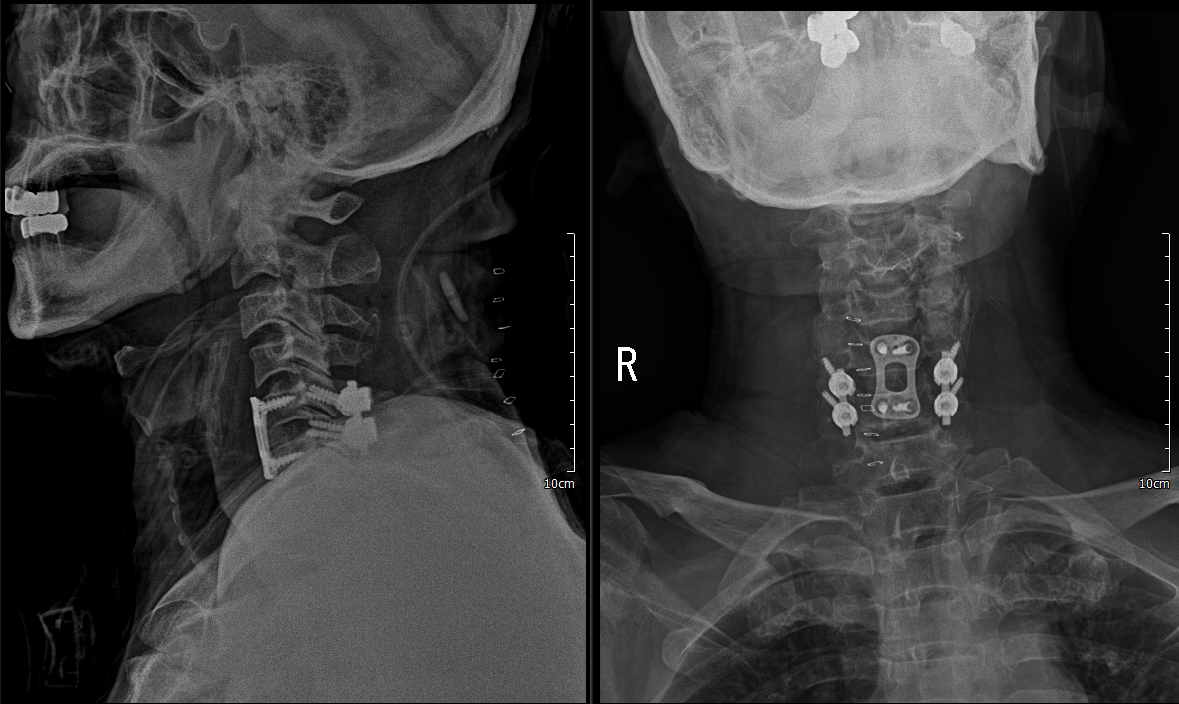

2. PF C5/6

하지만 안정성 확보를 위해 5일 후 뒤쪽으로 고정술 시행

lateral mass screw을 사용하여 고정술 시행

현재 POD 2일 째, barovac에서 배액은 잘 되고 있고, 첫 날보다 통증도 감소상태